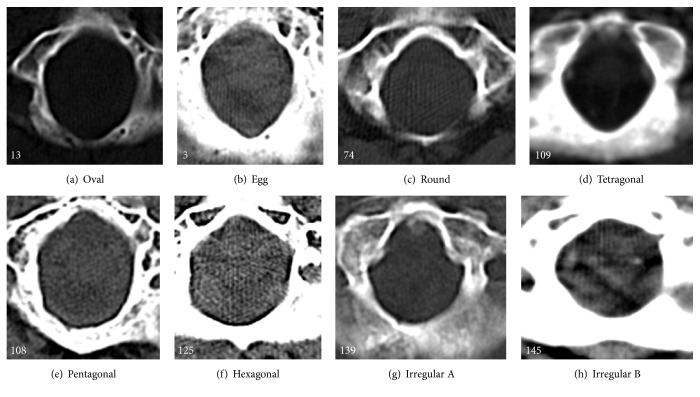

Materials and methods: The study sample comprised 200 CT scans (110 males and 90 females) of south Indian origin. The shapes of the foramen magnum were classified into 8 types: oval, egg, round, tetragonal, pentagonal, hexagonal, irregular (A), and irregular (B). The parameters were noted meticulously and the statistical analysis for sex comparison was made by Student's t-test and was considered significant whenever P≤0.05. To determine the relationships between the studied parameters, Pearson correlation coefficients were calculated.

Results: The foramen magnum was classified into 8 types based on shape. Commonest was oval and pentagonal was the least common type. The anteroposterior diameter, transverse diameter, circumference, and area were significantly greater in males than in females (P<0.001). The mean FM index of male CT scans was 85.01 ± 8.67, whereas in case of female CT scans, it was 83.17 ± 7.78. With all the variables in consideration, overall 65% of cranial CT scans were sexed correctly by using multivariate analysis.